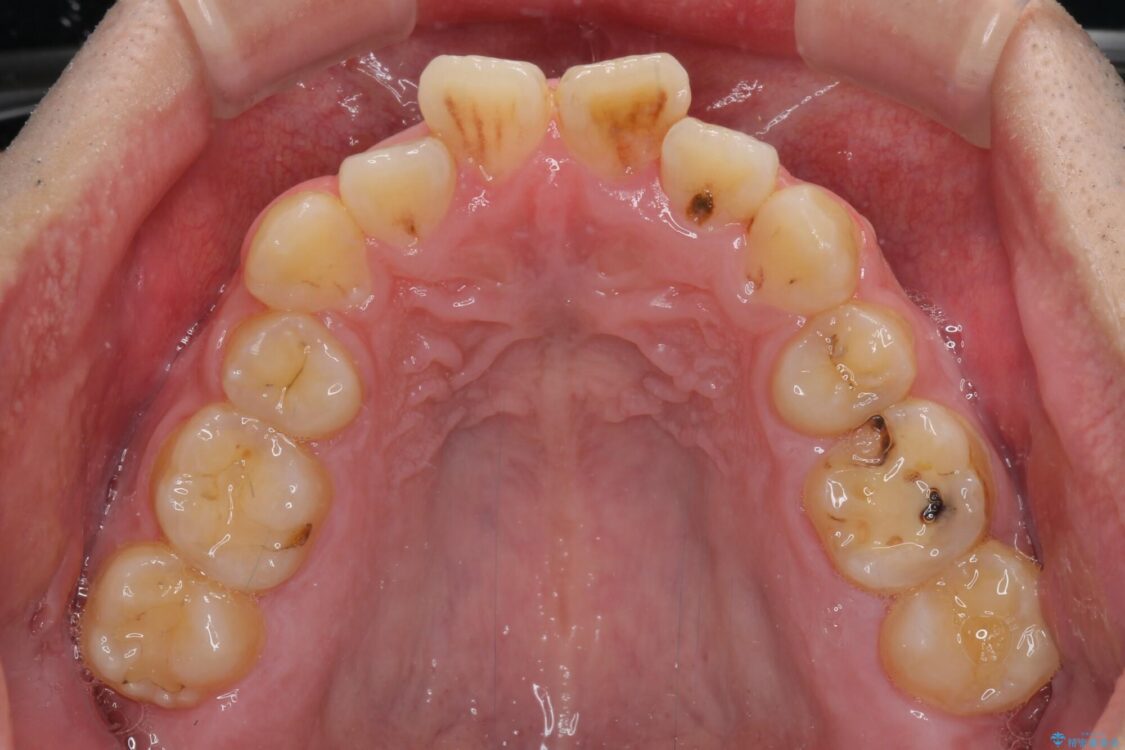

高校時代に行った抜歯矯正が後戻りをしたとのことで来院された患者様です。

治療前

• 後戻りでデコボコの前歯 インビザライン矯正治療 治療前画像